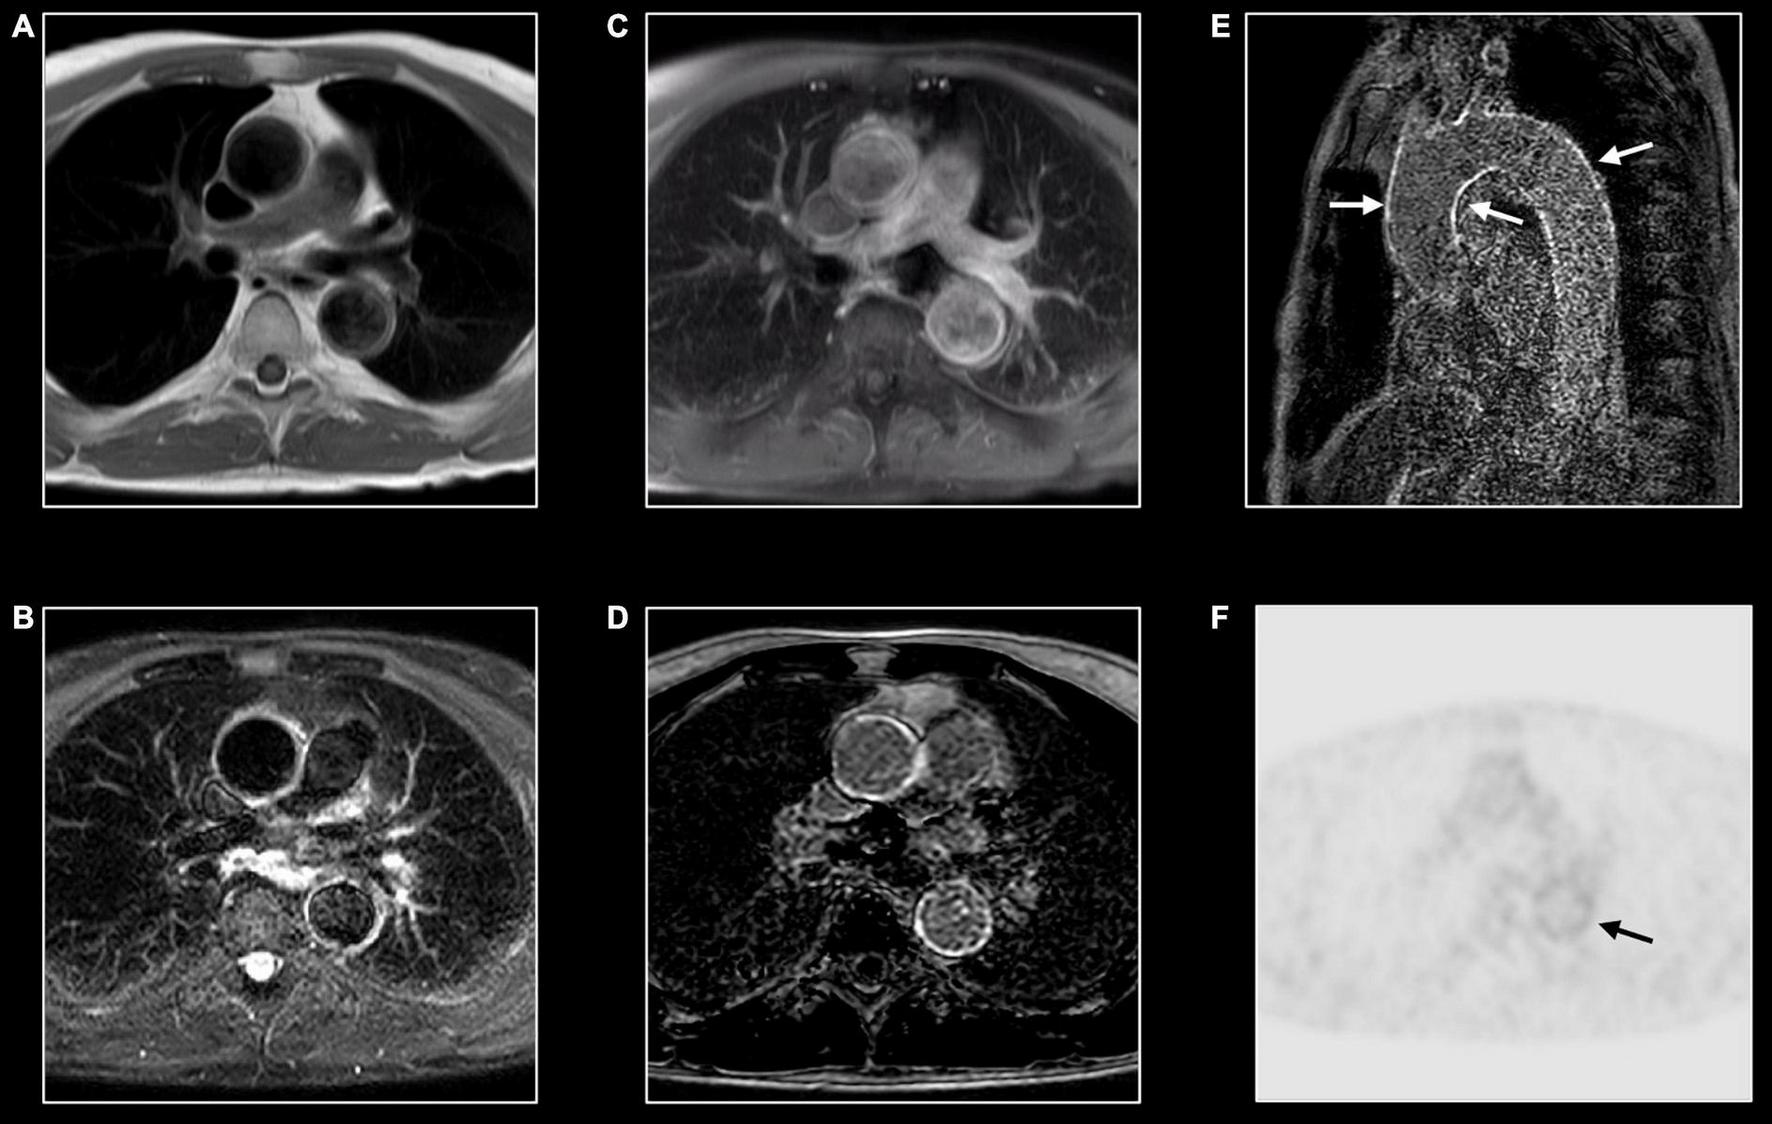

FIGURE 11

Immunoglobin G4-mediated aortitis in 57-year-old man. T1w imaging (A) shows mild dilatation of the proximal descending aorta with mild wall thickening. Hyperintense appearance of both ascending and descending aorta at T2w imaging (B) with contrast enhancement at post-contrast T1w imaging (C) and LGE imaging (D). A long-axis view through the thoracic aorta nicely shows the diffuse wall enhancement [arrows, (E)]. FDG-PET shows mild to moderate tracer uptake [arrow, (F)] in the descending aorta [arrow, (F)].

Inflammation of the aorta and its main branches are characterized by common features as mural thickening (i.e., >2–3 mm is considered diagnostic for aortitis), wall, and periaortic soft tissue edema on T2w images, and post-contrast enhancement (Figure 11) (66). Layering thrombus and ulcerative process may be also encountered.

Distribution and associated features differ by etiology. Extracranial giant cell arteritis is the most frequent etiology of aortitis with classical MRI signatures previously described. Significant wall thickening with consequent stenosis and aneurysmatic dilatation characterize Takayasu arteritis with specific involvement of aorta and main branches, more frequently subclavian arteries (Figure 4) (67). Pulmonary artery involvement has been reported in up to 70% of cases but the real prevalence is still unknown (68). Coronary ostial stenosis may lead to ischemic myocardial lesions detected by CMR as subendocardial LGE with different grades of segmental or global systolic dysfunction. Coronary involvement is the most concerning complication of Kawasaki disease with coronary artery dilatation, stenosis, thrombus formation, and possible myocardial ischemic lesions (Figure 5) (69, 70).

Immunoglobulin G4–related aortitis is characterized by an aggressive course with intense periaortic involvement and acute aortic complications (e.g., intramural hematomas and aortic dissections) (Figure 11) (71). Behçet disease is a multi-systemic vasculitis whose hallmarks are oral and genital ulcerations, arthritis and ocular involvement. Both arterial and venous vascular systems can be affected with consequent stenosis and/or dilatation. While pericarditis is the most common cardiac manifestation, myocardial involvement has been reported in literature (66). CMR provides useful information in case of mycotic aneurysm, syphilitic and tuberculous aortitis showing diffuse, or more frequently focal, wall thickening, edema, and contrast enhancement with or without aneurysmatic dilatation (66). Medium and small-vessel vasculitis may also cause cardiovascular complications. Apart from the aforementioned Kawasaki disease, polyarteritis nodosa may cause inflammatory stenosis and aneurysmatic dilatation of medium-size arteries, including coronary arteries. As previously mentioned, in patients with eosinophilic granulomatosis with polyangiitis (the former Churg-Strauss syndrome) CMR can show myocardial involvement similarly to other eosinophilic myocarditis with diffuse subendocardial LGE, systolic dysfunction, and intraventricular thrombosis (72).